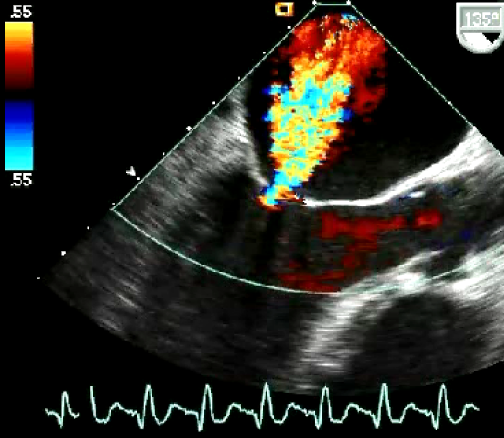

Curso de ecografía crítica en todas sus modalidades (ecocardiografía transtorácica y transesofágica, ecografía pulmonar, vascular, cerebral, FAST) dirigido a: médicos intensivistas, emergenciólogos, anestesiólogos, internistas, médicos de familia, neumólogos, cardiólogos y a todo aquel interesado por utilizar la ecografía como parte del examen físico del paciente crítico.

Como herramienta para diagnosticar de forma no invasiva el o los mecanismos generadores del shock / inestabilidad hemodinámica.

En nuestro afán por seguir el trabajo empezado hace ya varios años desde Europa (España) por impulsar la ecografía crítica para intensivistas, emergenciólogos, anestesistas, internistas, subespecialistas de obstetricia crítica, neumólogos y todo aquel médico interesado en aprender a utilizar la ecografía como parte de su examen físico, ahora desde Centroamérica (Panamá), hemos escrito el primer libro Latinoamericano-Europeo de ecografía crítica sub-especializado y dedicado exclusivamente al paciente con shock de cualquier etiología (obstructivo, distributivo, cardiogénico, hipovolémico) que involucra todas las modalidades ecográficas: ecocardiografía, ecografía pulmonar, vascular, abdominal, del sistema nervioso central/doppler transcraneal, etc) en el que participan muchos expertos en sus respectivas áreas tanto de Europa como de América y también algunos profesores del EDEC (Diploma Europeo de ecocardiografía / ESCIM- Sociedad Europea de Medicina intensiva).